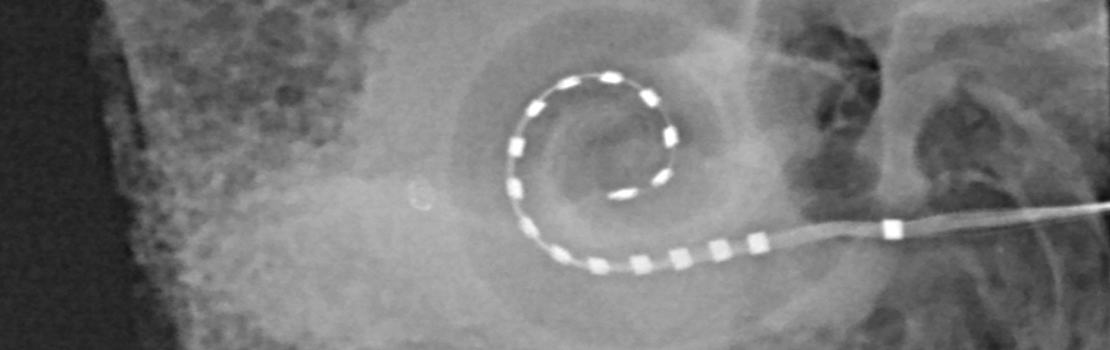

光学机是电子设备 外科移植到时间骨架上 头骨侧分机有两个主要元素:外部或声音处理器,耳后通常磨损,内部机体即移植体内部用外科移植入延时骨架-电极阵列插入cchlea声音与外部声音处理器并发并转换为电讯,电讯通过皮肤传递内部体移植体生成电脉冲,直接刺激耳神经,并以此方式绕过内部耳受损发细胞直接向脑神经提供电讯终于传递信息 通过主听通脑

自报和听力评测均有必要对CI处理结果形成更全面的透视证明CI、Dietz及其协作者Thomas Lenarz教授安全并从中受益,该教授来自汉诺威医学院,是欧洲CI主要中心之一主席,最近对接受局部麻醉术的病人进行了研究。外科团队在程序期间不得不与病人建立无缺陷通信关系,他们通过反耳听器(通过不受影响的耳机)、视觉辅助器或机机辅助器按需实现通信联系CI外科手术使用局部麻醉利多卡因留置听力病人外科小组可监控听力同时插入CI电极,以便根据病人反馈修改行为以这种方式,它们可以插入电极而不破坏精密耳结构以提供最好的听力后处理结果过程期间 病人在电物理测量期间 已经可以评析声道和声道感知与普通麻醉手术相比,研究对象可直接转至病房,无需在休眠室监视。

研究的正面结果令我们大吃一惊并不只是外科结果, 特别是病人接受局部麻醉下外科没有一个病人需要泛泛麻醉来完成程序,71%返回问卷者中97%对总体经验满意,84%者如果选择,将再次选择局部麻醉程序研究中共有27名病人接受余听并有资格电声振荡,他们根据实时反馈持续监控并调整电极阵列位置Petz表示:「在这些病人中我们使用局部插入概念,表示我们细单外科规划, 计及每个病人单耳大小和术前听力水平, 以便选择最优电极数组长度并判定插入该电极深度以取得最佳听力保护结果